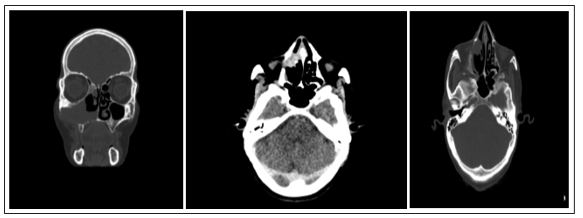

The clinical examination was carried out systematically and bilaterally from the first consultation, and which was carried out firstly without preparation of the nasal cavities and secondarily after preparation based on wicks soaked in xylocaine naphazoline 5%. This examination made it possible to show: a gray, unilateral, multi-lobed and bleeding tumor process on contact in all patients. All cases underwent facial CT visualized a unilateral tumor process extending to the maxillary sinus (Figures 2, 3, 4).

Figures 2, 3, 4: Naso-ethmoido-maxillary lesional process with moderate bone

aggressiveness increases heterogeneously after injection of the contrast product (facial TDM) Total tumor removal was the therapeutic alternative chosen for all patients. The macroscopic examination of the samples received at the pathology service was fragmented material in all cases, measuring between 0.5 and 5 cm. It was brownish in color, firm in consistency and the site of hemorrhagic changes. Histological examination showed a papilllomatous polypoid respiratory mucosa, invading the level of the chorion with signs of low grade dysplasia in only one case (Table I), (figures 5, 6, 7).